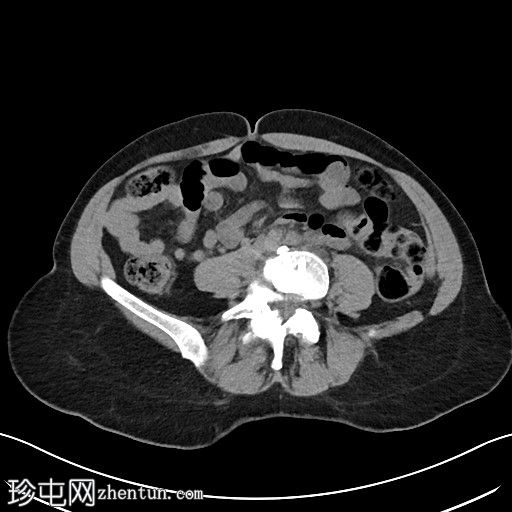

2.jpg

冠状位

平扫

左侧腹膜后可见一巨大囊性肿块,位于左侧腰大肌内侧,紧邻多个手术夹(ALIF手术所用),这些手术夹紧贴囊性肿块后壁。

膀胱已行引流管减压,并被囊性肿块向右侧推移。

子宫和左侧附件在囊性肿块前方保持正常的脂肪间隙,因此附件囊性病变的可能性较小。

左侧输尿管难以辨认,因为它位于囊性肿块下缘后方。